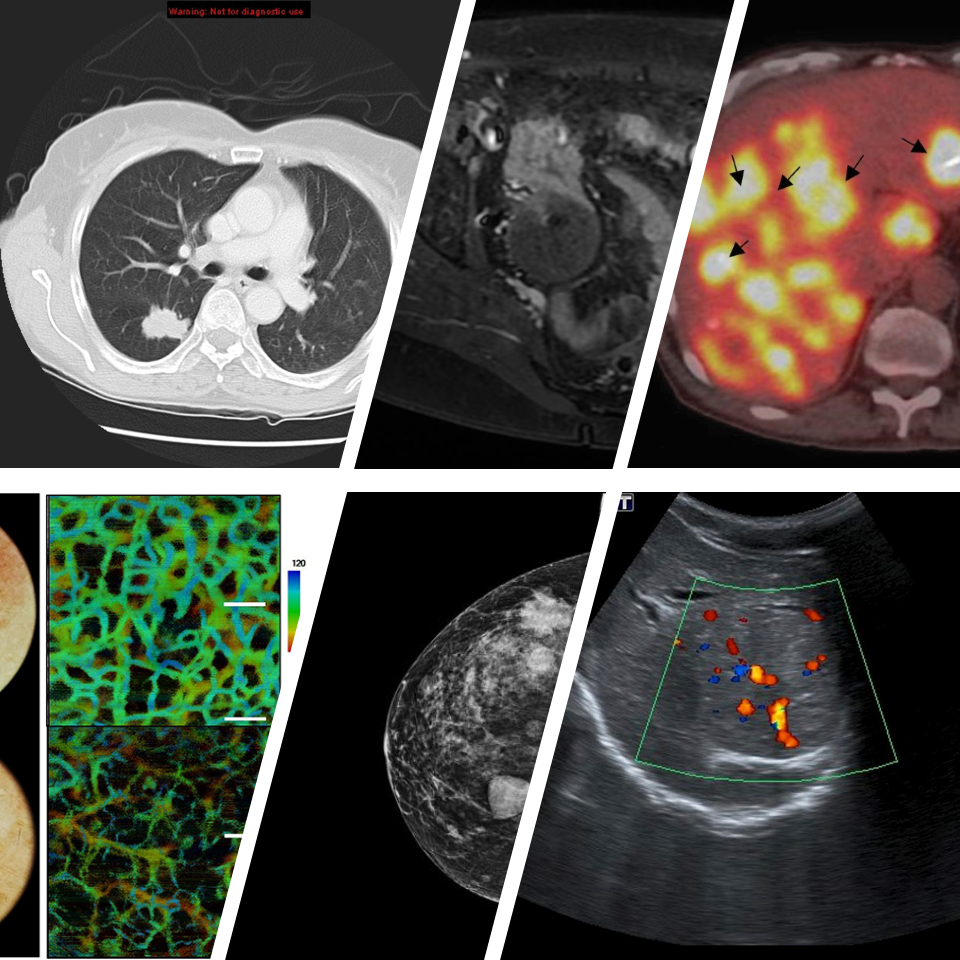

Cancer Imaging Types

The NCI Cancer Imaging Program fosters advances in in vivo medical imaging sciences through support of basic and applied research in cancer imaging as well as promotion of imaging in clinical trials in order to gain greater understanding of the pathways of cancer biology for the benefit of cancer patients and people at cancer risk.

Cancer Imaging: visualize the problem and direct the solution.